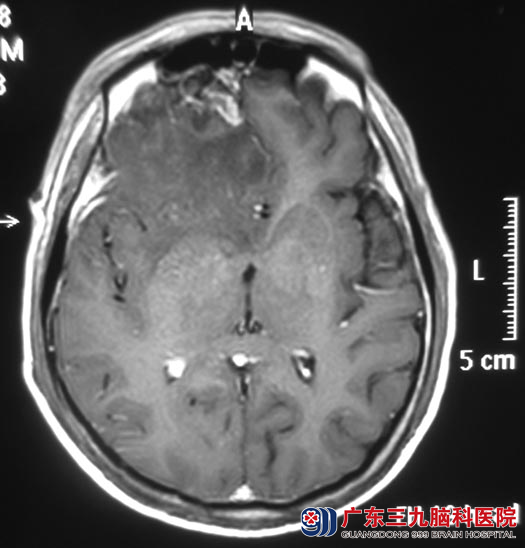

广东三九脑科医院进一步头颅MR检查提示:右侧额叶占位,大小约3cm×3cm,考虑脑膜瘤可能性大。

9月1日,由综合神经外科 鲁明主任主刀,在全麻下行右侧额部脑膜瘤切除术,术中显微镜下见脑组织受压,肿瘤位于右额底,紧邻矢状窦,肿瘤呈红白色,质地硬,血运一般,与脑组织边界较清,在镜下予肿瘤全切,手术顺利。一周后王先生即康复出院。术后病理结果为:过渡型脑膜瘤(WHO I级)。